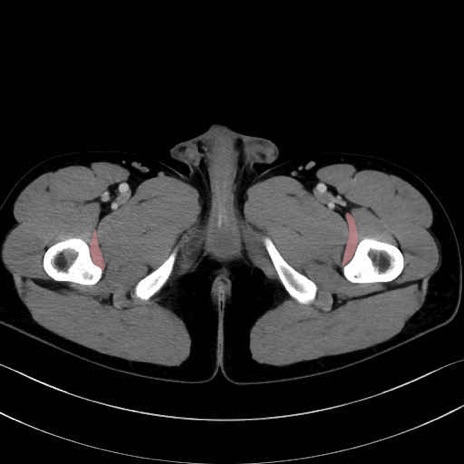

外閉鎖筋 (Obturator externus)

大腿方形筋 (Quadratus femoris)